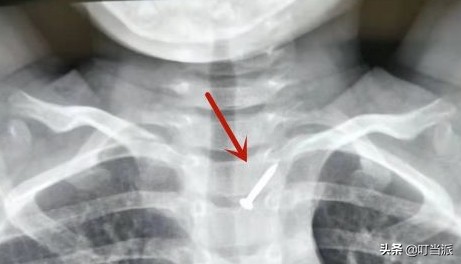

4岁的福州男孩明明(化名)不知怎么的,就吞下近2厘米长钉子!

父母得知后赶忙将儿子送往医院。

接诊医生赶紧给孩子查了CT,发现一枚钉子扎在孩子的食管上,危险的是,边上就是颈总动脉。

福建省福州儿童医院消化内科主任林卫东介绍道:这颈总动脉若是扎破,就像自来水打开龙头一样,血液喷出的高度近两米,分分钟会危及孩子生命。

图片来源:福州日报